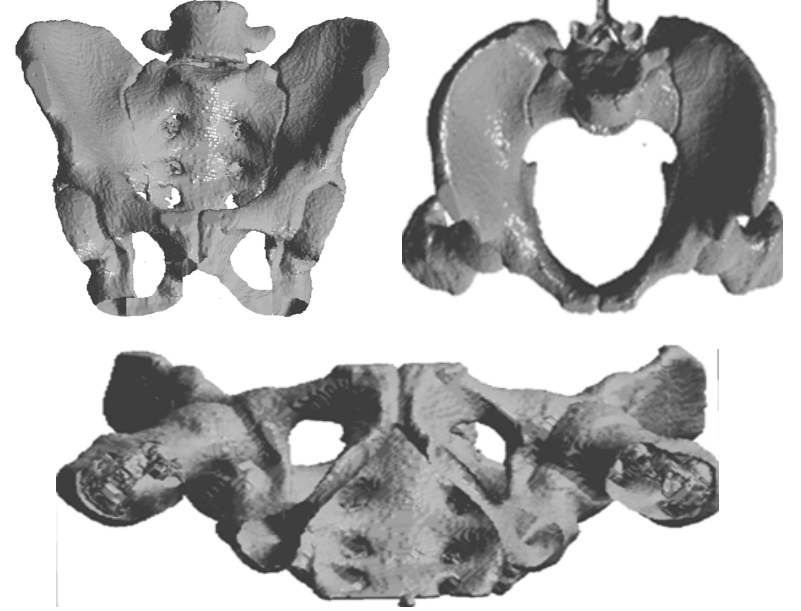

- 아래 사진은 최종적으로 재구성한 3D 모델이다.

- 위 3D 모델의 표면 윤곽은 일반적으로 선택된 관심 영역의 경계에서 파생된 여러 개의 겹치는 다각형으로 모델링된다. 보간 기술을 이용하면 더 나은 결과를 얻을 수 있을 것이다.